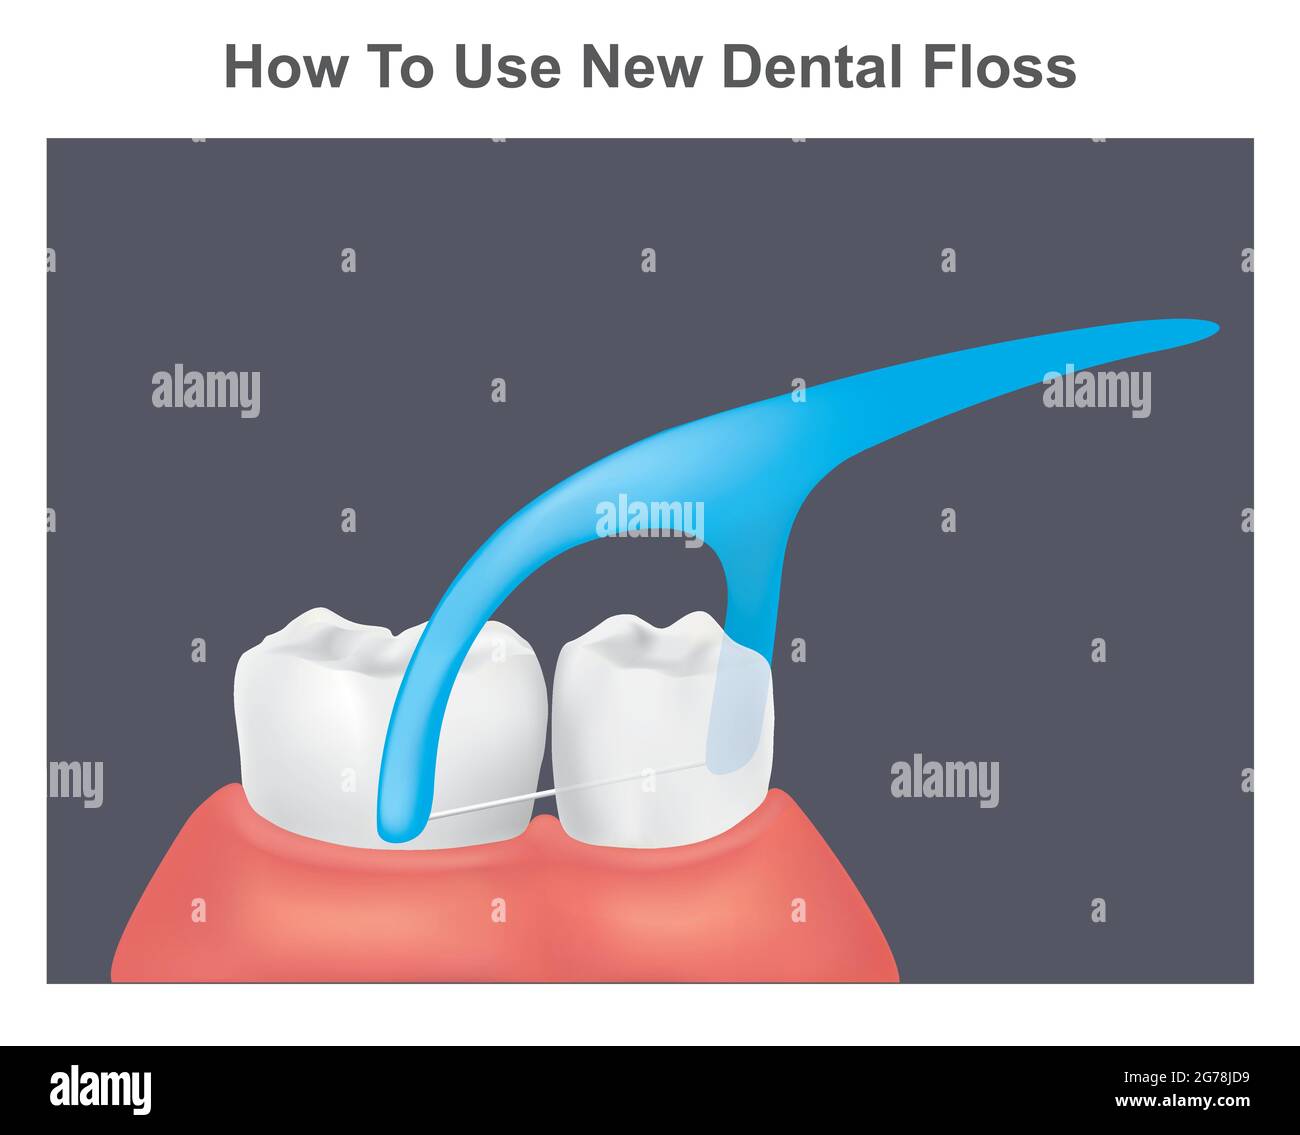

Come usare il filo interdentale nuovo. Illustrazione di denti e gengive sani usando il nuovo filo interdentale. Illustrazione Vettorialehttps://www.alamy.it/image-license-details/?v=1https://www.alamy.it/come-usare-il-filo-interdentale-nuovo-illustrazione-di-denti-e-gengive-sani-usando-il-nuovo-filo-interdentale-image434751893.html

Come usare il filo interdentale nuovo. Illustrazione di denti e gengive sani usando il nuovo filo interdentale. Illustrazione Vettorialehttps://www.alamy.it/image-license-details/?v=1https://www.alamy.it/come-usare-il-filo-interdentale-nuovo-illustrazione-di-denti-e-gengive-sani-usando-il-nuovo-filo-interdentale-image434751893.htmlRF2G78JD9–Come usare il filo interdentale nuovo. Illustrazione di denti e gengive sani usando il nuovo filo interdentale.